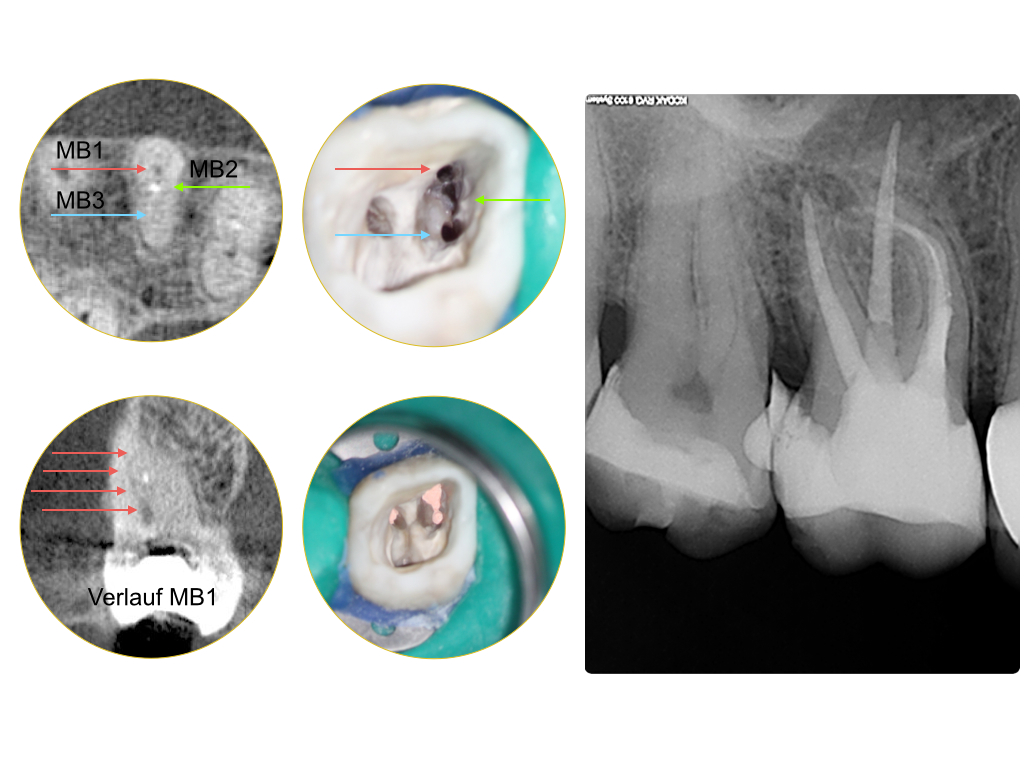

Instrumentenfrakturen (2)